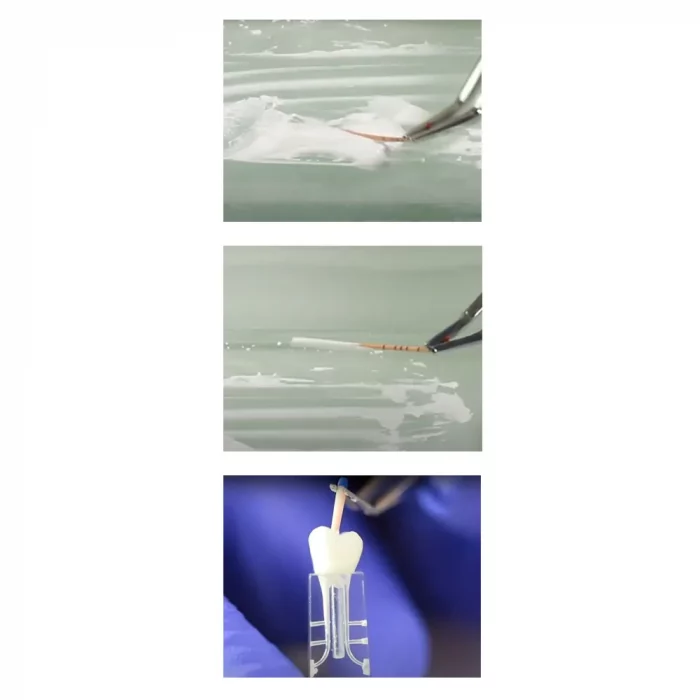

- Uses cold single cone or cold lateral condensation

Septodont’s BioRoot™ RCS is a revolutionary bioactive mineral root canal sealer that harnesses the power of their patented Active Biosilicate Technology. With high mineral purity and a monomer-free composition, BioRoot™ RCS ensures optimal biocompatibility and reduces the risk of adverse reactions. It promotes hydroxyapatite formation at the tooth-sealer interface, aiding in the mineralization of the dentinal structure for enhanced long-term stability. The sealer exhibits antimicrobial properties, effectively combating bacterial growth and minimizing the chances of reinfection. Its resistance to microleakage contributes to a durable and reliable seal. Additionally, BioRoot™ RCS provides excellent radiopacity for clear post-operative assessment. Its easy handling and retractable properties, simplifying application during procedures. Notably, BioRoot™ RCS is MR-safe, posing no risks or interactions within magnetic resonance imaging environments. It is also safe for use during pregnancy, offering added peace of mind. Ideal for the permanent root canal filling in a variety of cases, including vital or necrotic pulp situations and retreatment procedures, BioRoot™ RCS can be utilized with either the single cone technique or cold lateral condensation.

- BioRoot™ RCS provides permanent root canal filling with gutta-percha points in various pulp cases and retreatments.